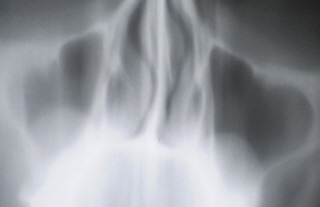

Иллюстрация 18 демонстрирует наличие кистозных образований в базальных отделах гайморовых полостей.

Для сравнения приводится томограмма этого пациента в оптимальном срезе – иллюстрация 19, которая четко демонстрирует, что томограмма, даже в оптимальном срезе, по сравнению с цифровым изображением дополнительной информации «не несет».